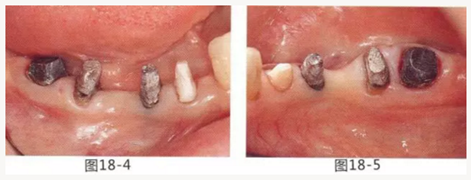

圖18-4 去除臨時修復體后的頰側面照。在手術前去除右下5,6,7的金屬樁可以使手術更為方便。右下5,6部位基本看不到角化牙齦。

圖18-5 同部位的舌側面照片。角化牙齦較少,將牙槽嵴頂預測切開的話很有可能會沒有任何角化牙齦。